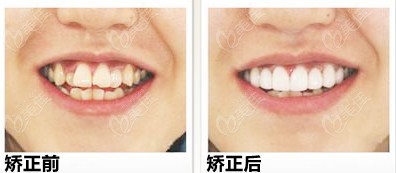

6、牙齿矫正后会后悔吗,会留下一辈子的后遗症

矫正不会有后遗症。事实上,约50%的矫正患者需要拔牙。在正畸治疗过程中,牙齿受力移动时会有轻微松动,但经过正畸治疗后一段时间的维护,牙齿周围的牙槽骨会得到重建,牙齿会变得像以前一样稳定,不用担心老了会掉牙。牙齿矫正的费用也与牙齿矫正的医院和方法有关。在一些权威医院,有名的正畸价格更高。相对来说,一些中小型正畸机构收费起点较低,但往往不能保证效果好。